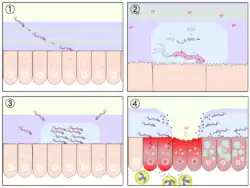

Ferner wird auch eine mögliche Übertragung durch Schmeißfliegen diskutiert. Die Besiedlung mit H. pylori erfolgt ausgehend vom Antrum cardiacum der Speiseröhre aboral in Richtung Mageneingang (Kardia) und Magenpförtner (Antrum pyloricum). Hierbei bewegt sich der Keim durch Geißelschlag fort. Spezialisierte Haftstrukturen ermöglichen ihm die besonders feste Anbindung an die Epithelzellen der Magenschleimhaut, die die Voraussetzung für das entzündliche Geschehen darstellt.

Im Magen schützt sich der säureempfindliche H. pylori vor der Zerstörung durch Magensäure

- durch Einnistung in und unter der Magenschleimhautbarriere (Schleim, der die Magenschleimhaut vor Selbstverdauung schützt) und

- durch die Spaltung von Harnstoff in Ammoniak und Kohlendioxid, wobei Ammoniak den pH-Wert in der unmittelbaren Umgebung des Keims anhebt (neutrales Mikromilieu, „Ammoniakmantel“). Diese Reaktion wird durch das von H. pylori produzierte Enzym Urease katalysiert, welches auch dem diagnostischen Nachweis dient (Helicobacter-Urease-Test).

Die durch die Urease-Reaktion gebildete Ammoniakmenge ist normalerweise gering und bei intakter Magenschleimbarriere nicht toxisch. Vielmehr werden folgende schädigende Vorgänge beschrieben.

- H. pylori sezerniert eine Reihe von schleimhautschädigenden und die körpereigene Immunabwehr paralysierenden Enzymen. Die Entzündung führt zu einer vermehrten Gastrin- und infolgedessen zu einer vermehrten Magensäureproduktion. Dennoch verlaufen viele Typ-B-Gastritiden symptomlos. Nicht selten lässt erst eine zusätzliche Schwächung der Magenschleimhautbarriere (beispielsweise durch Alkoholkonsum, Nikotin, Arzneimittel, Stress usw.), die den Keim vorübergehend zu einer vermehrten Ammoniakbildung veranlasst, um sich selbst zu schützen (Ammoniaksprung),[6] ein Geschwür entstehen, meist im Bereich des Pylorus oder im Zwölffingerdarm.

- H.-pylori-Stämme vom Typ I weisen zusätzliche Pathogenitätsfaktoren auf und sind stark krankheitserregend in Bezug auf die gastroduodenale Ulkuskrankheit und auch Krebs. So ist ein grundlegender Auslöser die Exprimierung des entzündungsfördenden sogenannten vakuolisierenden Zytotoxins (VacA Genprodukt). Wie Cesare Montecucco zwischen 1993 und 2000 nachwies, bewirkt es die Bildung von kleinen Zellsafträumen (Vakuolen) in den Epithelzellen, die sich bis zum Zerplatzen mit Säure füllen und damit das Gewebe zerstören.

- Einen weiteren Mechanismus fanden Forscher des Institut Pasteur in Paris. Demzufolge injiziert das Bakterium über einen nadelartigen Fortsatz ein Peptidoglycan ins Innere der Magenepithelzelle. Dort dockt dieses an einen Rezeptor an und setzt eine Reaktionskette in Gang, die letztlich zur Entzündung der Magenschleimhaut führt.[7] Der Mechanismus ist genetisch codiert, der entsprechende Abschnitt auf dem Bakterienchromosom wird als „Zytotoxin-assoziierte-Gene-Pathogenitätsinsel“ (engl. cytotoxin-associated genes (cag)[8] pathogenicity island) bezeichnet.